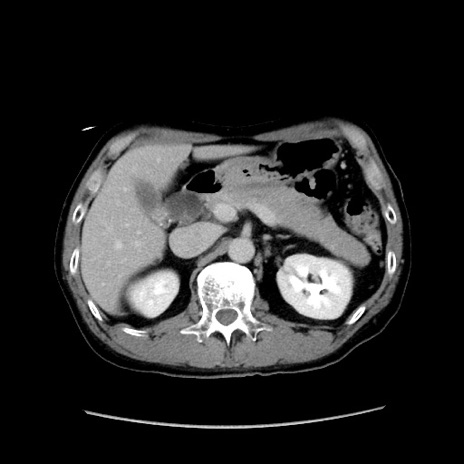

冠状断像

【症例】40歳代 男性

【主訴】腹痛

【現病歴】4時間ほど前に電車に乗車中に臍部上より腹痛出現。徐々に増悪し起立困難となり、救急外来受診。生ものは数日食べていない。今朝お雑煮を食べた。

【身体所見】BT 36.8℃、BP 117/84mmHg、HR 91/min、SpO2 97%、苦悶様、腹部:臍上部広範囲圧痛あり、反跳痛±

【データ】WBC 8100、CRP 0.03